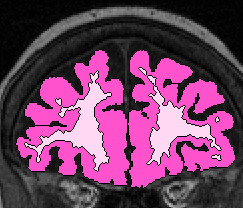

| Procedure for White Matter Parcellation: Frontal Lobe White Matter: Change "cerebral white matter" on every slice that has frontal lobe present on it to "frontal lobe white matter." This will, on some slices, for the time being, change some white matter that is actually temporal or parietal white matter to frontal lobe white matter. This will be corrected later on, however. |  (fig 1) |